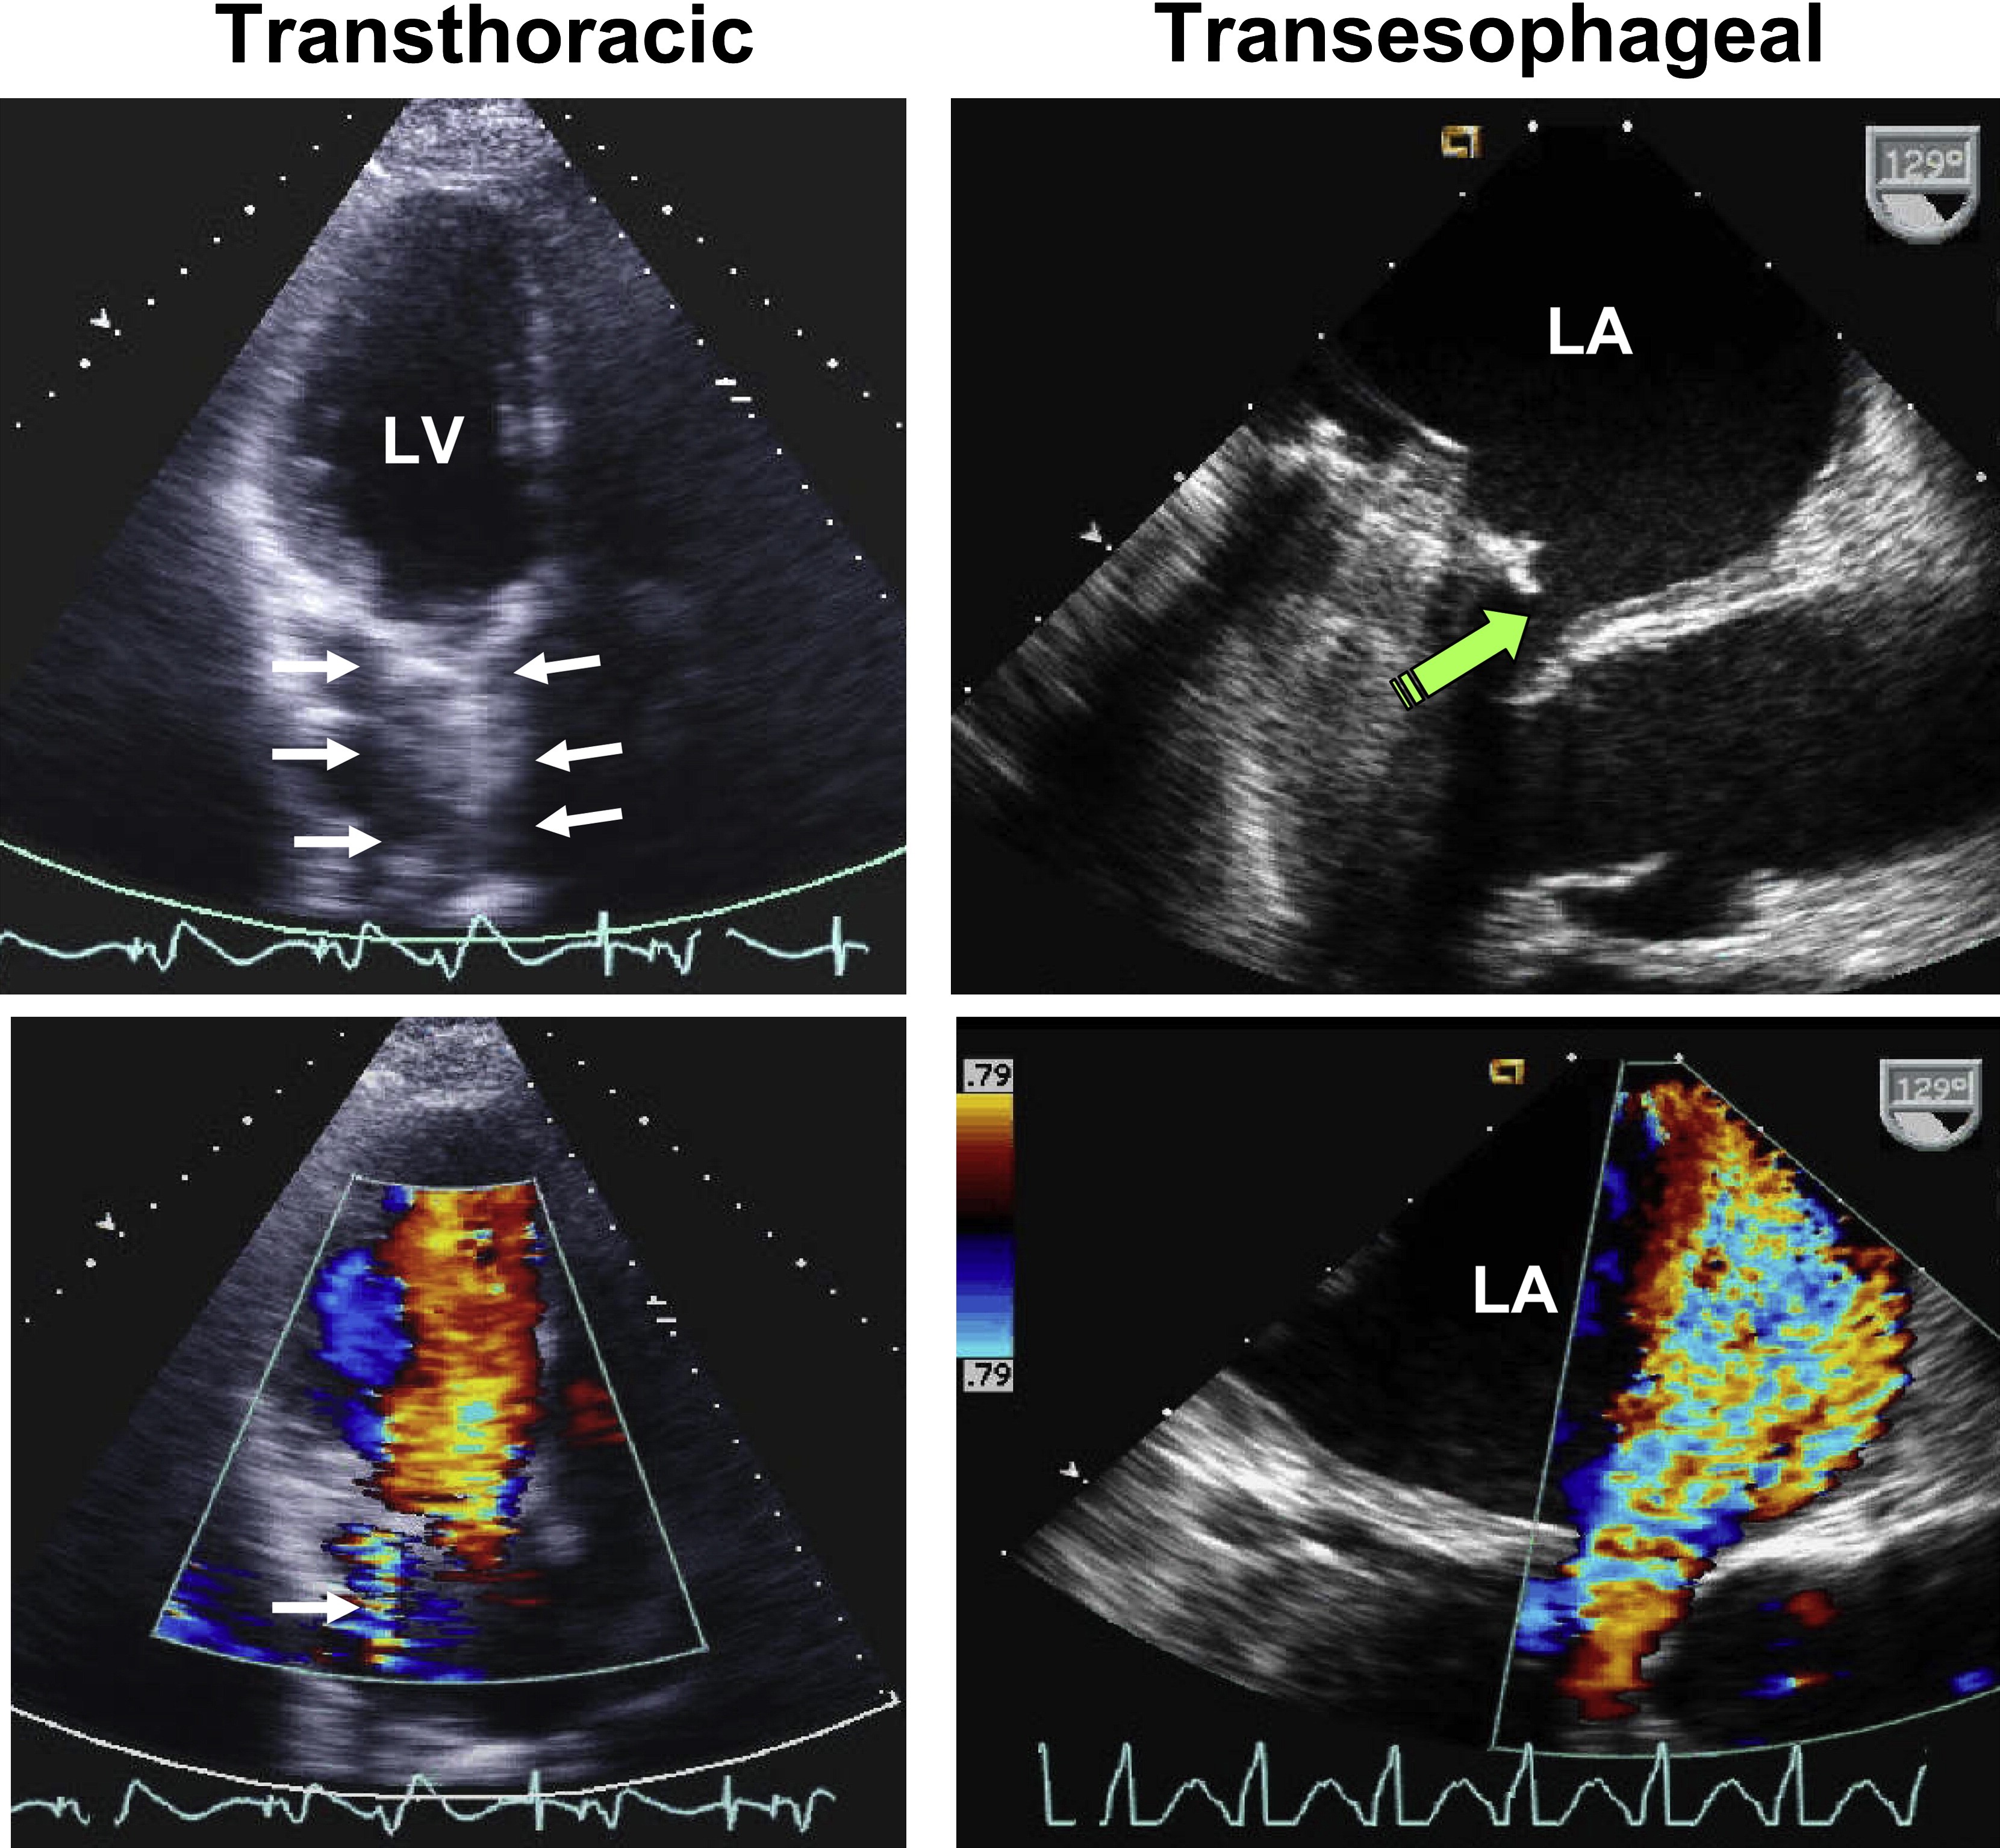

# Immediate Surgical Attention 需要立即手术治疗的情况

- Risk of geometric mismatch 几何学不匹配的风险

- Moderate to severe valvular regurgitation 中度至重度瓣膜返流

- Significant paravalvular leak 严重的瓣周漏

- 'stuck' mechanical valve leaflets 机械瓣瓣叶卡住

- Valve dehiscence 瓣膜裂开

- Transthoracic versus transesophageal echocardiographic and Doppler images in a patient with severe paravalvular MR.

严重瓣周 MR 患者的经胸超声心动图和经食管超声心动图和多普勒图像。 - Shadowing on TTE of the left atrium (arrows) masked significantly the regurgitant jet by color Doppler (single white arrow).

左心房 TTE 上的阴影(箭头)通过彩色多普勒(单白色箭头)显着掩盖了反流束。 - The extent of valvular dehiscence is shown by the green arrow on TEE as well as the severity of regurgitation by color Doppler.

瓣膜裂开的程度由 TEE 上的绿色箭头表示,反流的严重程度由彩色多普勒表示。